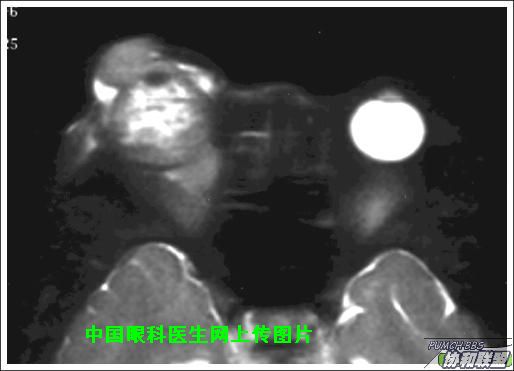

出院后半年发现右眼出现肿物,增长较快,随来京再次就诊(图1),转来我科。门诊检查发现:右眼无光感,结膜下肿物,突出睑裂。眼球突出,上移位。眶外侧可触及硬性肿物。超声(图2),CT(图3),MRI(图456)显示如图.

此主题相关图片如下:

图片点击可在新窗口打开查看